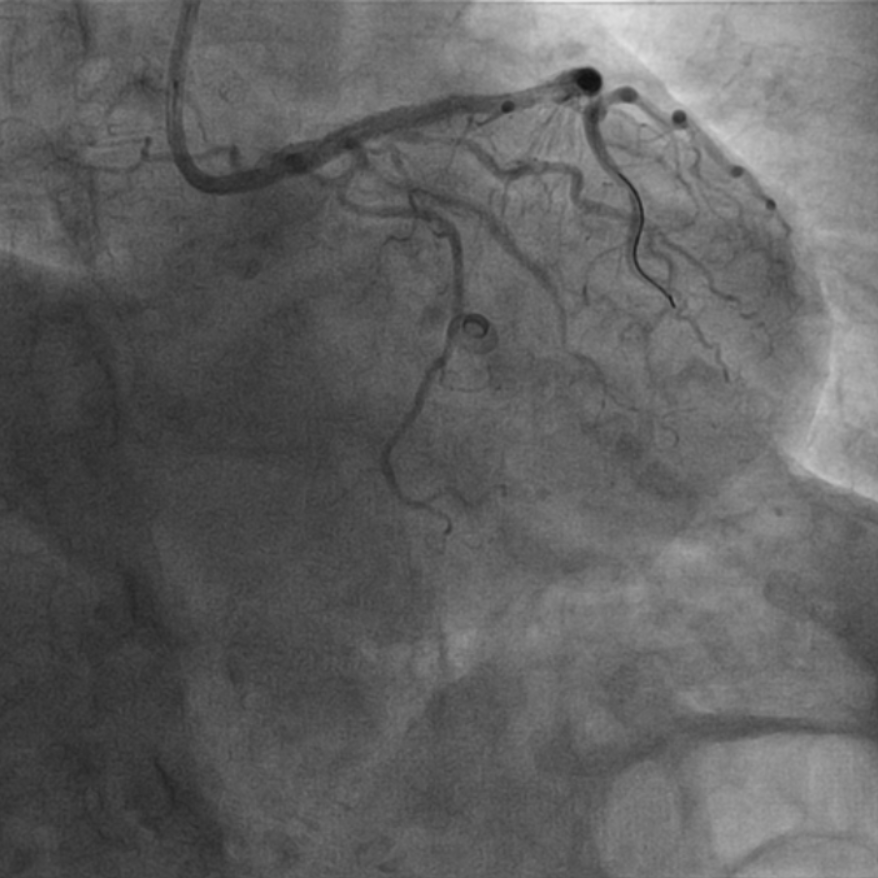

图3 IVUS示右冠中段支架膨胀不良,支架内多处可见新生钙化病变

该患者入院后,完善相关检查并再次建议行CABG治疗,但家属仍拒绝,遂考虑再次行PCI手术干预。冠脉造影提示患者冠脉右冠状动脉中段70-95%再狭窄,左主干末端80%狭窄,前降支原支架中远段 80-95%再狭窄,回旋支完全闭塞,急需手术尽快解决冠脉血流灌注问题,否则随时有生命风险,但患者多处支架内/节段内再狭窄,造影提示钙化明显,外院已尝试无法扩张,经手术团队充分讨论后,计划在IABP支持下,先进行右冠状动脉干预,利用IVUS精准评估原支架再狭窄部位情况,采用旋磨或Shockwave冲击波球囊处理无法扩张的病变部位,右冠处理后择期进行左冠状动脉干预。在制定了详尽的手术计划后,手术团队首先对患者的右冠状动脉行IVUS检查,结果提示该患者右冠中段支架局部膨胀不良,局部支架面积6.67mm²,管腔内多处可见钙化小结及270°以上钙化,IVUS钙化积分达3分。由于膨胀不良处原支架后方可见钙化斑块,常规旋磨效果不佳,对于此类钙化病变,IVL处理是最佳方案。手术团队对近端采取棘突球囊及高压球囊进行扩张,采用Guidezilla辅助下输送3.0mmx12mm Shockwave冲击波球囊于右冠钙化处进行冲击波钙化斑块碎裂术,通过IVUS证实支架内的新生钙化病变得到松解,原膨胀不良部位支架面积达到7.76mm²,后经过高压球囊充分预处理,顺利完成右冠支架植入,术后复查右冠原膨胀不良部位支架面积9.17mm²。